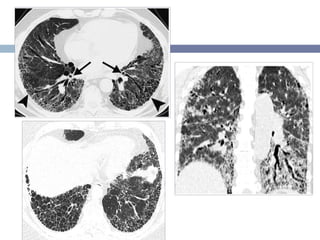

• #32 Atypical appearances of COP. (a) CT image shows bizarrely shaped nodules, some of which are cavitating (arrow). (b) CT image shows perilobular opacities that resemble thickened interlobular septa (arrow).

• #33 El patrón radiológico puede ser similar La consolidación predomina en los campos pulmonares superiores y tiene una distribución subpleural. NSIP de 75 años. Opacidades en vidrio despulido bilateral y en parche, con ausencia de panal de abejas.